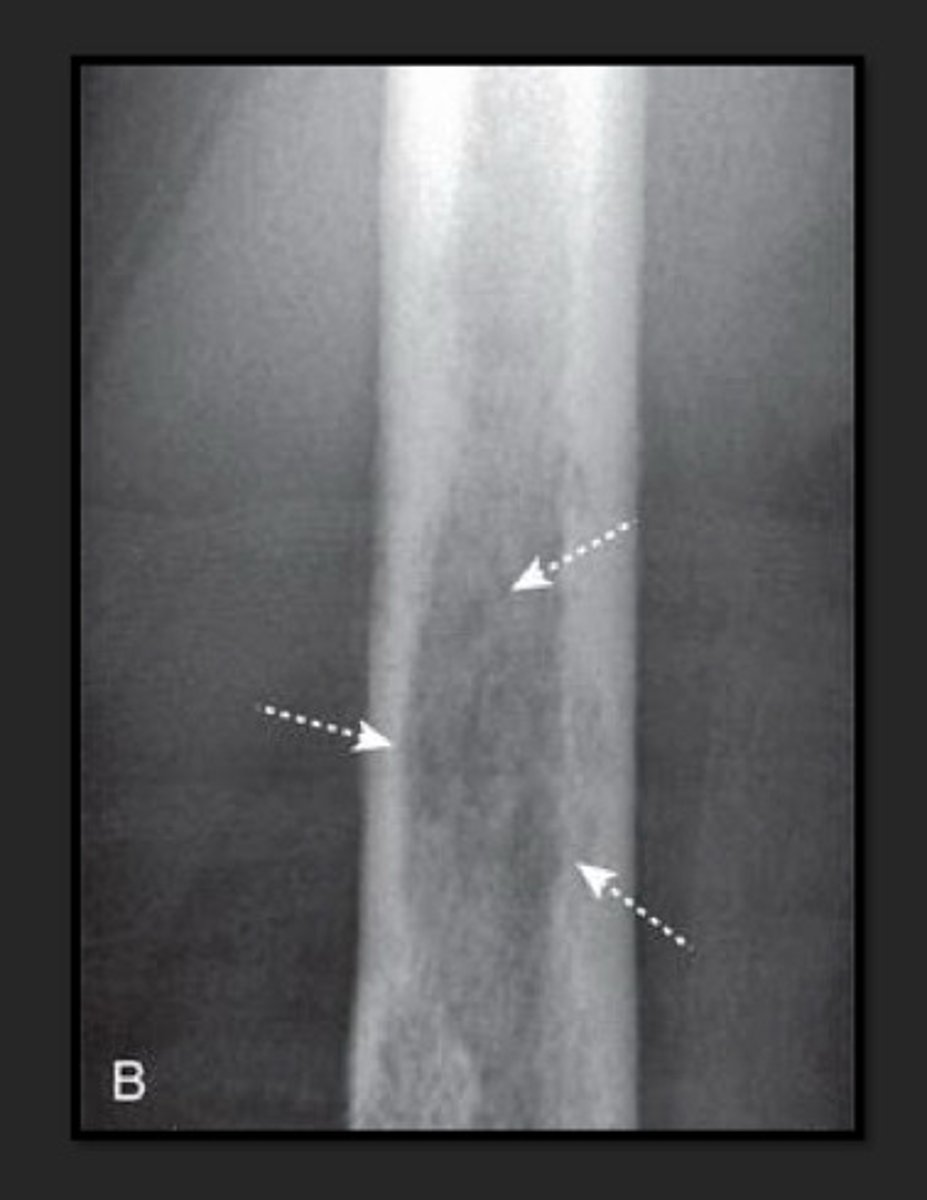

fracture

disruption in the continuity of all or part of the cortex(hard outer layer) of a bone

incomplete fracture

only part of the cortex is fractured

complete fracture

through & through

through all 3 elements: growth plate, metaphysis and epiphysis; more likely to develop early fusion of growth plate w/ angular deformities & shortening of bone

type V salter harris fracture

crush injury to growth plate; more likely to develop early fusion of growth plate w/ angular deformities & shortening of bone; associated w/ vascular injury & cause growth impairment